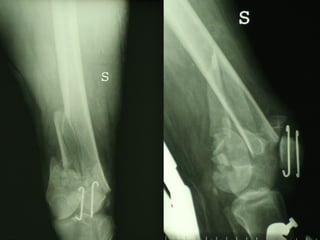

Dal Gennaio 2000 al Febbraio 2006 abbiamo trattato 167 fratture chiuse  con placca percutanea  in 164 pazienti :  27 lesioni diafisarie di gamba, 12 piloni tibiali ,  11 fratture prossimali di tibia, 36 fratture sovracondiloidee di femore, 17 fratture diafisarie di femore, 43 fratture metaepifisarie prossimali di omero, 21 diafisarie d’omero.  156 guarigioni 8 fallimenti

I buoni risultati ottenuti dipendono da 5 punti fondamentali:   una accurata riduzione percutanea della frattura  precise vie di accesso  l’utilizzo della placca che consenta il più lungo braccio di leva possibile il pretensionamento della placca  una sintesi con un ridotto numero di viti

Precise vie di accesso

Placche lunghe e pretensionate

Placche lunghe e pretensionate Sintesi con un ridotto numero di viti

VANTAGGI CHIRURGIA MININVASIVA Mini Open Inserimento della placca sottocutaneo per scivolamento Viti percutanee Preservazione dei tessuti molli Ridotto danno vascolare Rapida ripresa funzionale

Conclusioni Riduzione  anatomica Minimo trauma chirurgico Corretto equilibrio fra elasticità e stabilità Precoce mobilizzazione